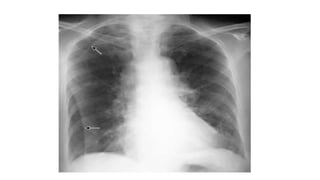

A normal chest x-ray shows the lungs, heart, bones, and soft tissues appearing healthy and unobstructed. The document discusses the different views used in chest x-rays, including PA, AP, lateral, and lateral decubitus views. It also covers topics like depth of inspiration, rotation exposure, the lobes of the lungs, identifying the heart, and how to read a normal chest x-ray.